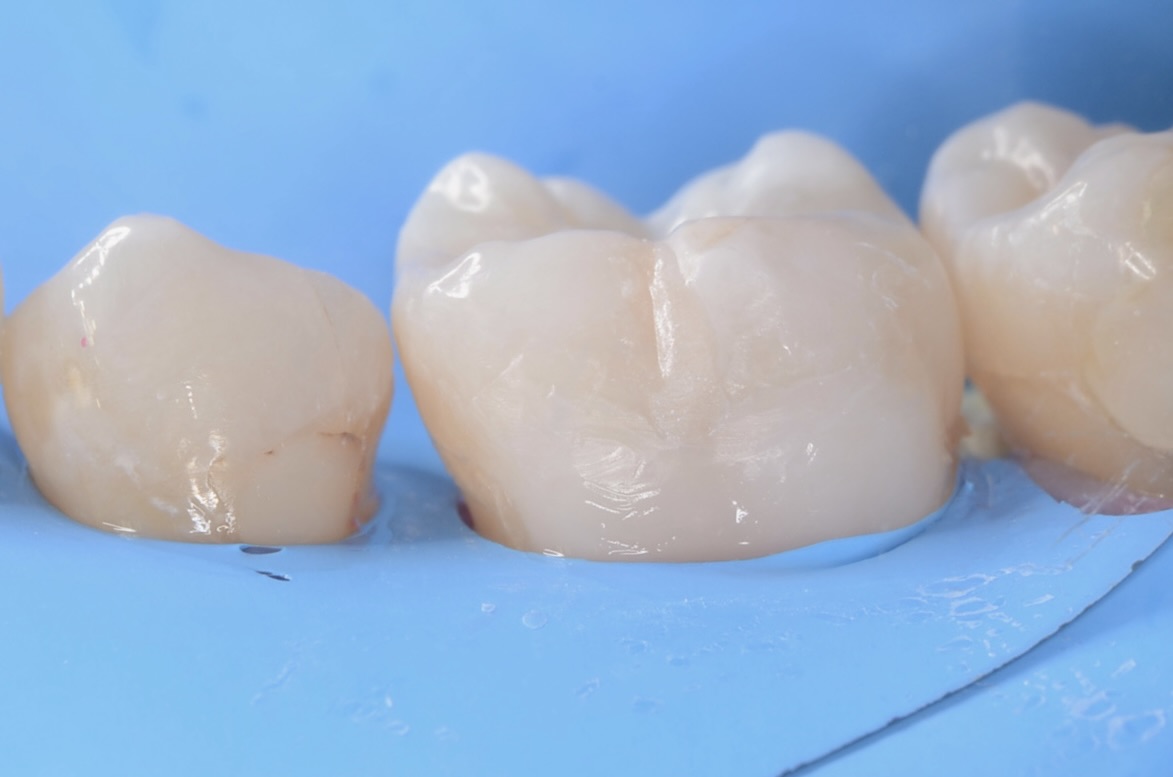

3Dプリンターテクニック

フロワブルレジンを用いて、その表面張力を利用して滑らかで段差のないレジン充填を実現させます。 セパレーターで歯間離開させながら光を当てながらレジンを硬化させる3Dプリンターテクニックを用いて治療しました。 -

ダイレクトボンディング終了

咬合面にはペースト状のレジンで、形態を作りました。天然歯の自然な形態を模倣してレジンを充填しました。 -